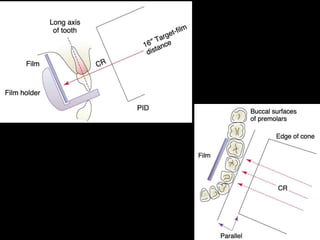

1. The document discusses various intra-oral radiographic techniques including the paralleling cone technique and bisecting angle technique.

2. The paralleling cone technique provides accurate images with little magnification and no superimposition but is more difficult for patients. The bisecting angle technique is easier for patients but results in more image distortion.